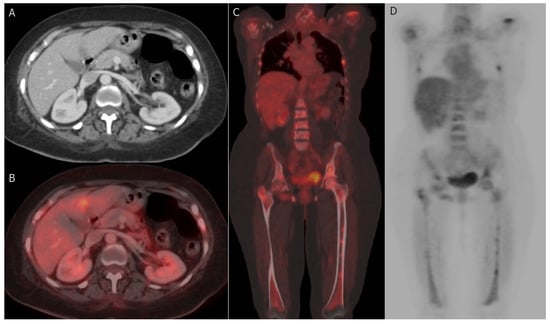

7.2.1. PET-CT

- PET-CT has a critical role in systemic staging and the detection of tumor response and recurrence of BC, but PET-CT has low sensitivity to diagnose primary BC compared to other dedicated breast imaging [144].